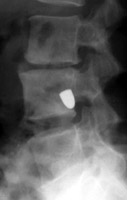

Tumbling Bullet Sign

Two sets of frontal and lateral radiographs, separated only by time, which reveal the "tumbling bullet sign"--which is simply a bullet which changes its location and orientation within a solitary bone cyst. This sign serves two purposes. It is documentation of the evolution of a solitary bone cyst as a corollary of trauma, and reveals the free movement of the foreign body within the confines of the lesion establishing its cystic rather than solid nature. It is similar to the fallen fragment sign.

- Click on the image for a larger versionA - Click on the image for a larger versionB - Click on the image for a larger versionC - Click on the image for a larger versionD